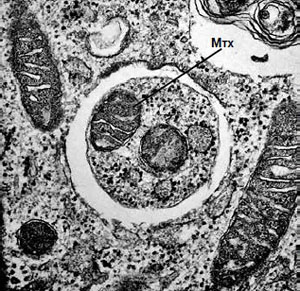

Аутофагия в фибробластах мыши, выращенных на бедной питательными веществами среде. Хорошо видна митохондрия (Мтх) внутри аутофагосомы. Изображение: Nature Cell Biology, 2010, 12, 823–830

Во время диплома Осуми изучал синтез белков у кишечной палочки, но выдающихся результатов не получил. Молекулярно-биологических лабораторий в Японии того времени было не так много, найти работу казалось сложно. Получив степень в 1974 году, Осуми отправился в США — в Рокфеллеровский университет, где стал постдоком у нобелевского лауреата Джеральда Эдельмана. Там ему пришлось переключиться на биологию развития млекопитающих, и он вспоминает об этом периоде без восторга. Но именно в лаборатории Эдельмана он приобрел опыт работы с дрожжами Saccharomyces cerevisiae, который пригодился ему впоследствии.